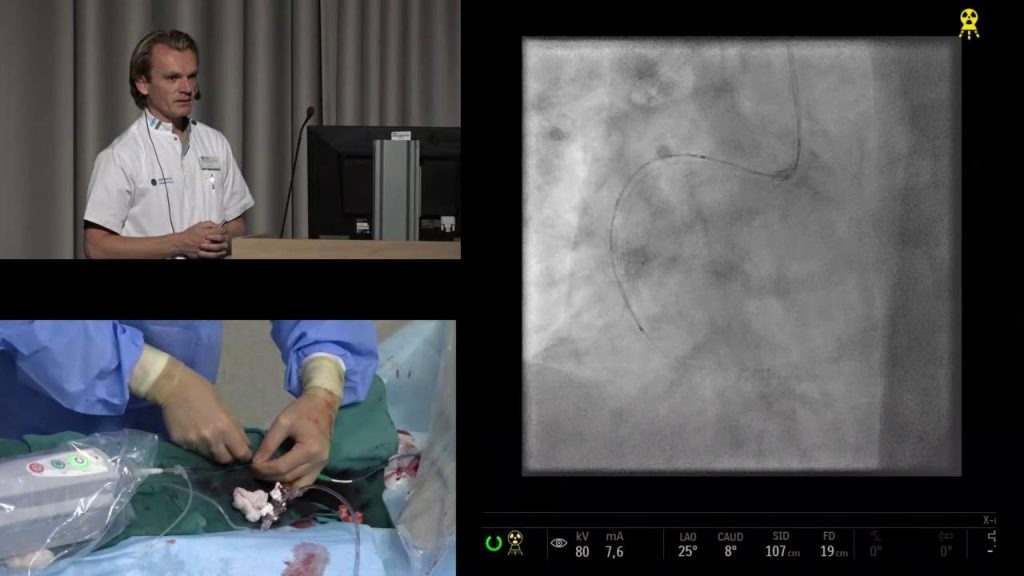

FFR-meting

FFR is een afkorting van Fractional Flow Reserve. Met een FFR-meting kunnen hartspecialisten tijdens een dotterbehandeling de bloeddruk voor en achter de vernauwingen in de kransslagader meten. Op deze manier kan er onderscheid gemaakt worden tussen onschuldige en potentieel gevaarlijke vernauwingen. “Inmiddels wordt deze in het Catharina Ziekenhuis ontwikkelde FFR-meting wereldwijd toegepast in alle grote hartcentra en heeft de procedure ervoor gezorgd dat er minder stents nodig zijn, dat de behandeling goedkoper is en dat de ziekenhuisopname korter is geworden. Nog belangrijker; hartpatiënten die gedotterd zijn op basis van bloeddrukmetingen vóór en achter de vernauwingen in een kransslagader hebben na vijf jaar nog altijd 30 procent minder kans op hartdood dan patiënten die volgens de traditionele manier zijn geholpen”, aldus cardioloog dr. Pim Tonino.